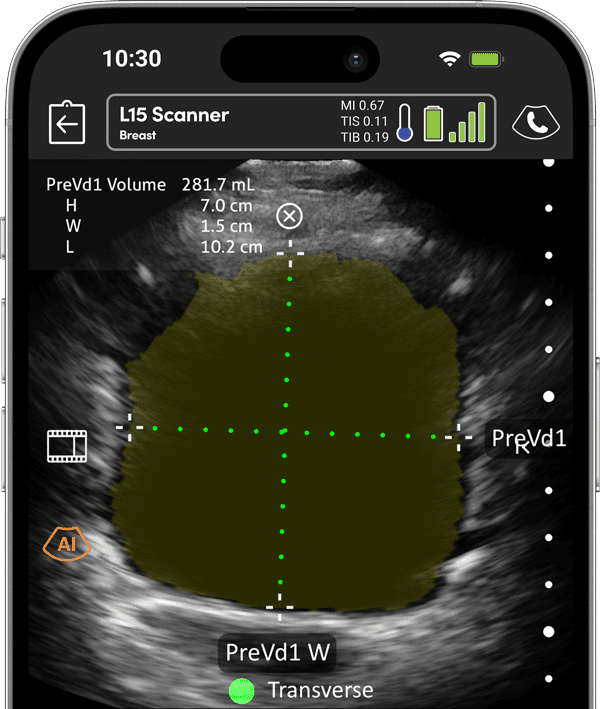

クラリアス膀胱AI

尿失禁、尿閉、神経因性膀胱機能障害などの膀胱および下部尿路(LUT)疾患の診断精度と治療を、AIを活用してより迅速かつ正確に評価することで強化する1。